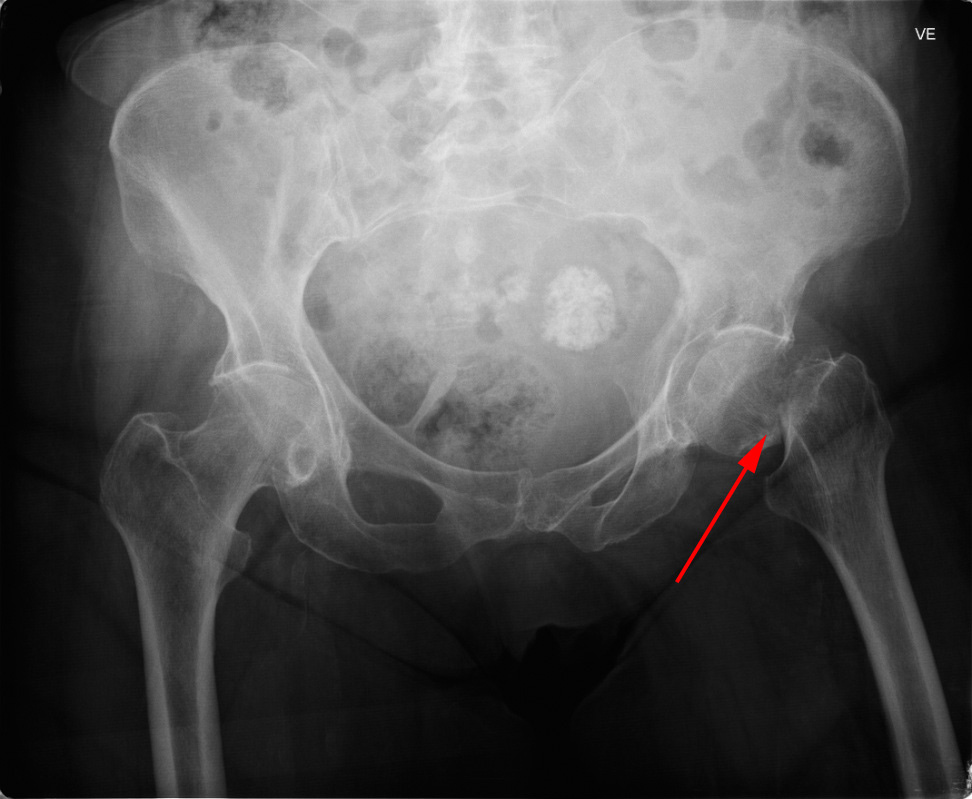

Røntgenundersøgelse af bækkenet der viser en hoftefraktur gennem lårbenshalsen (rød pil).